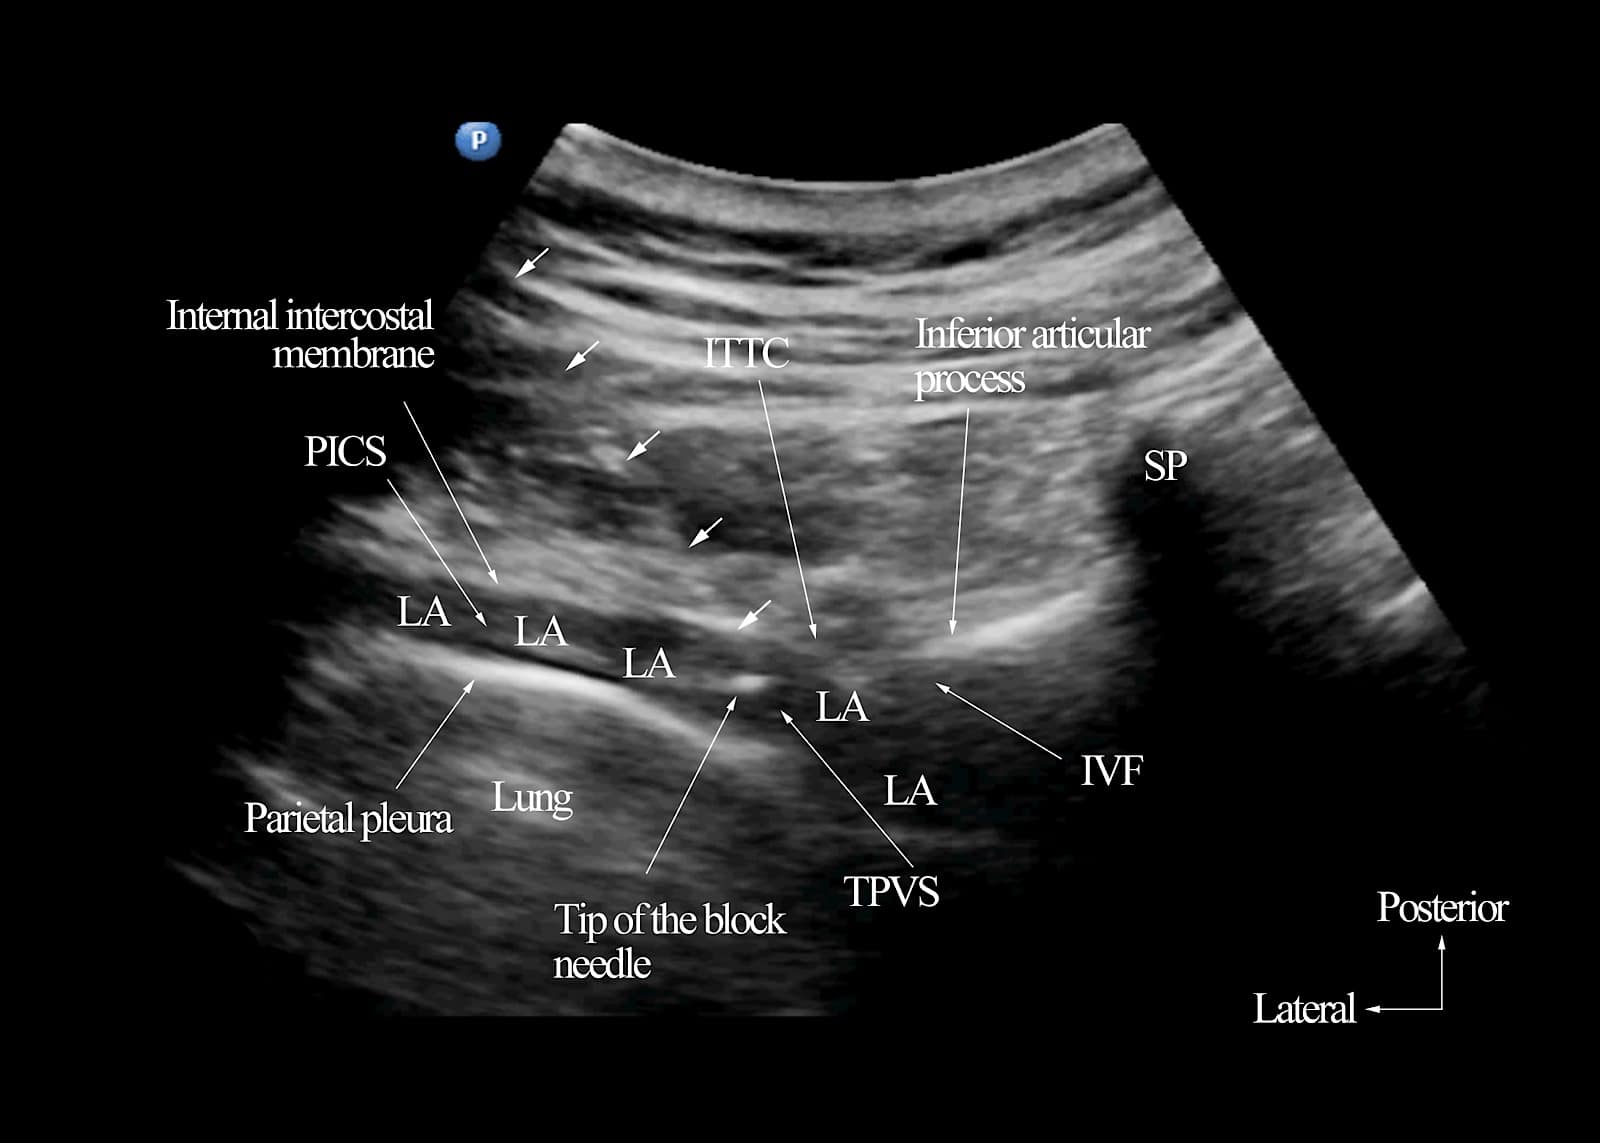

USG TPVB Using the Transverse In-plane Approach at the IAP Level

Under strict aseptic precautions, and with the target transverse ultrasound window at the IAP level in view (Figure 8), the nerve block needle is introduced in-plane from a lateral-to-medial direction (Figure 8B).11,62,63 The needle is advanced under real-time ultrasound guidance with a gentle back-and-forth (jiggling) motion until the needle tip is embedded within the ITTC. Interestingly, it is not uncommon to lose track of the needle tip once it enters the ITTC, possibly because the needle and ITTC are isoechoeic (Figure 8C). The needle is advanced in small increments followed by a 1-2 ml of 0.9% saline test bolus. Swelling of the ITTC or an anechoic fluid-filled area within the ITTC indicates that the needle tip is still within the ITTC. Entry of the needle tip into the TPVS is visualized as anterior displacement of the parietal pleura, widening of the paravertebral space, and increased pleural echogenicity upon saline injection (Figures 8D and 13).11,62,63 A calculated dose of LA is then injected in small aliquots.11,62-64 For multi-level USG TPVB, such as for primary breast cancer surgery, we use 3-4 ml of 0.5% ropivacaine or levobupivacaine with 1:200,000 epinephrine per level, with the total volume capped at 25 ml (125 mg) for the 6 injections (T1-T6).11,62,63 For perioperative analgesia, 20-25 ml of the same LA is injected at a single-level (T3-T4 for PBCS).64

Figure 13. Transverse sonogram of the thoracic paravertebral region after a single-injection ultrasound-guided thoracic paravertebral block (25 ml volume) at the inferior articular process level. Note the position of the intervertebral foramen (IVF) relative to the inferior articular process. Multiple small white arrows have been used to demonstrate the path of the block needle. The tip of the block needle is near the apex of the paravertebral space and away from the IVF. Also, note there is a widening of the thoracic paravertebral space (TPVS) and spread of the local anesthetic to the medial aspect of the TPVS and laterally to the posterior intercostal space.

SP = spinous process, ITTC = intertransverse tissue complex